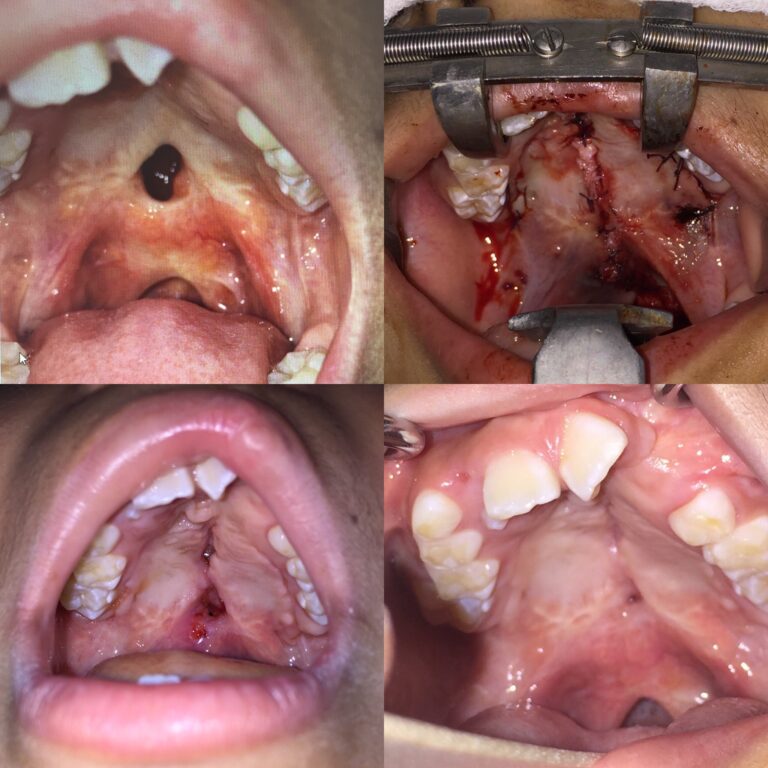

Cirugía de Paladar en pacientes con fisura labiopalatina. Técnica Asensio.

Cirugía de secuela de fisura de paladar, cerrada con Técnica Asensio...